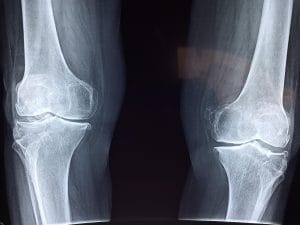

Knesmerter er vanlig blant både idrettsutøvere og mosjonister – spesielt hos dem som løper, hopper eller driver med mye styrketrening. To av de vanligste belastningsskadene i kneet er Jumper’s knee og Runner’s knee. Jumper’s knee er en vanlig plage blant idrettsutøvere der det forekommer mye hopping og eksplosive bevegelser. Volleyball og basketball er eksempler på idretter hvor dette er utbredt, men det er heller ikke uvanlig i mindre eksplosive idretter som fotball. Runner’s knee er mer vanlig i idretter med repeterende bevegelser, slik som løping – som navnet tilsier. Dette er imidlertid ikke den eneste idretten hvor tilstanden oppstår; vi ser det også ofte hos syklister og skiløpere. Riktig vurdering og behandling er avgjørende for å komme raskt tilbake i aktivitet.

Jumper’s knee

Runner’s knee